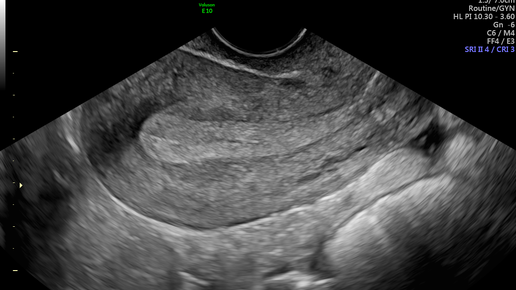

Эндометрий — это слизистая оболочка матки, которая создает оптимальные условия для имплантации эмбриона. Она состоит из двух слоев: верхнего функционального, который отторгается каждый месяц вместе с менструацией, и нижнего базального, который является своего рода фундаментом для верхнего. Как растет эндометрий Толщина эндометрия постоянно меняется в течение цикла в ответ на гормоны. В первой его части яичники вырабатывают эстрогены, которые влияют на эндометрий, стимулируя его рост. А после овуляции,...

Мой ответ: яичники вырабатывают и эстрогены, и прогестерон. Эстрогены заставляют эндометрий расти, а прогестерон сдерживает рост эндометрия. Перед менопаузой яичники дают сбой. От этого может нарушиться баланс эстрогенов и прогестерона. Если эстрогенов относительно больше, то эндометрий растет. Плюс, эстрогены могут вырабатываться жировой тканью вообще без всяких яичников. У прогестерона это плохо получается. Плюс, месячные могут прекратиться, и наросший эндометрий не отваливается, а только утолщается...